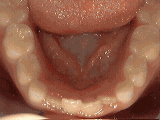

Sometimes braces are not needed to get noticeable improvements in tooth alignment. This patient was

first seen at age seven for crowding of the lower permanent teeth. A procedure was performed to reduce

the width of the adjacent baby teeth and the permanent incisors aligned on their own in nine months.